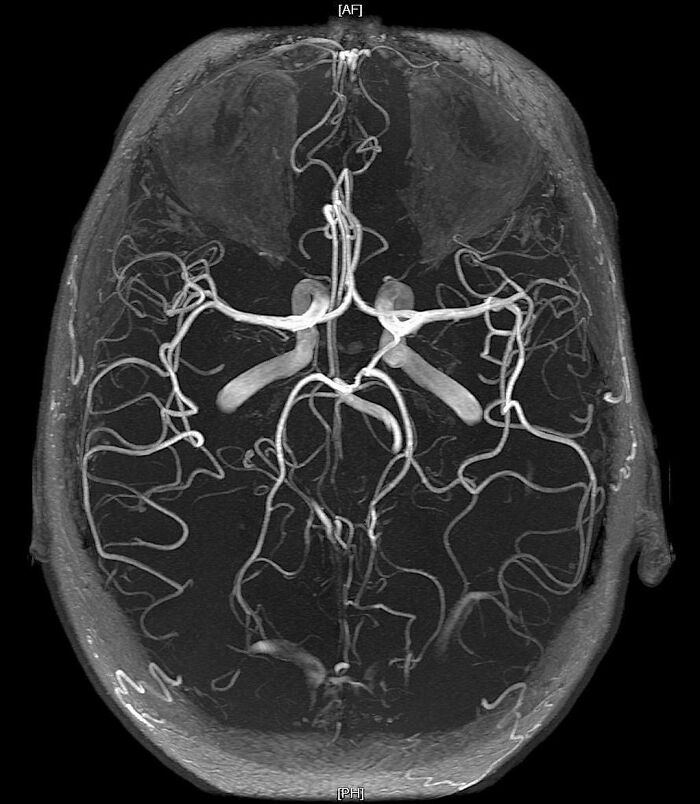

#78

Magnetic resonance angiography (MRA) of the brain